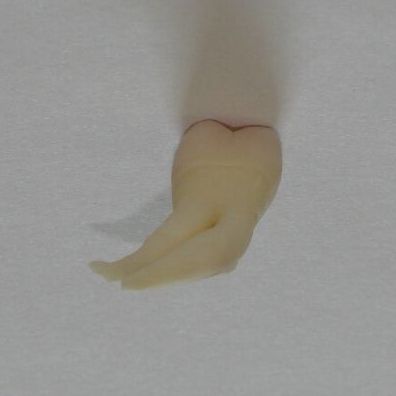

Trzykanałowa górna czwórka, nieczęsty przypadek.